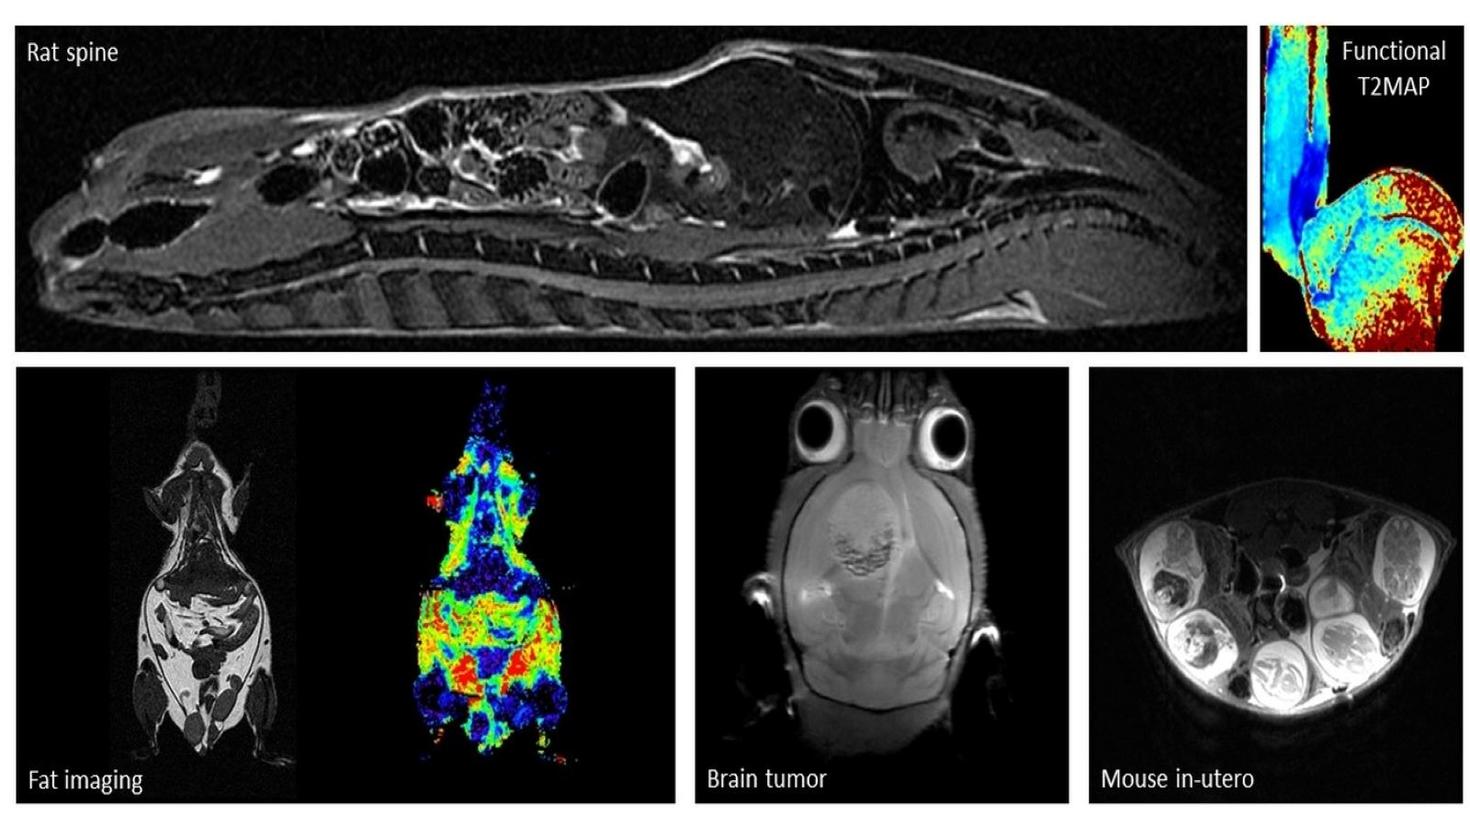

Le Centre abrite le seul appareil d’IRM pour petits animaux à grand champ de la région d’Ottawa (système Discovery MR901 de 7,0 Tesla d’Agilent Technologies / General Electric). Il n’y a qu’environ 10 machines de ce type dans tout le Canada qui offrent une occasion unique de tirer parti de cette ressource et d’obtenir un avantage dans le contenu de votre manuscrit.

Le système d’IRM est équipé d’un aimant supraconducteur à alésage horizontal de 7,0 T et 310 mm de diamètre, interfacé avec la plateforme Signa HDx de General Electric. Le système offre des capacités de recherche préclinique en IRM de haute qualité et robustes avec une variété de contrastes d’imagerie et d’évaluations quantitatives. CIPC fournit un service pour répondre à un large éventail de besoins des chercheurs, de l’imagerie d’animaux vivants aux recherches d’échantillons, la caractérisation d’agents de contraste à la recherche de matériaux et de plantes.

L’imagerie est réalisée à l’aide d’un puissant système de gradient de 300 mT/m (30 Gauss/cm) (diamètre intérieur de 210 mm) équipé d’une capacité de cale d’ordre 2. Une large gamme d’antennes de radiofréquence (bobines) sont disponibles, allant des antennes de corp aux antennes de réception dédiées et activement découplées pour le cerveau de souris et de rats. Des systèmes de surveillance physiologique et de manipulation des animaux sont également disponibles. Le spectromètre IRM est équipé de capacités X-nuclei.

Exemples d'images acquises par notre IRM 7T